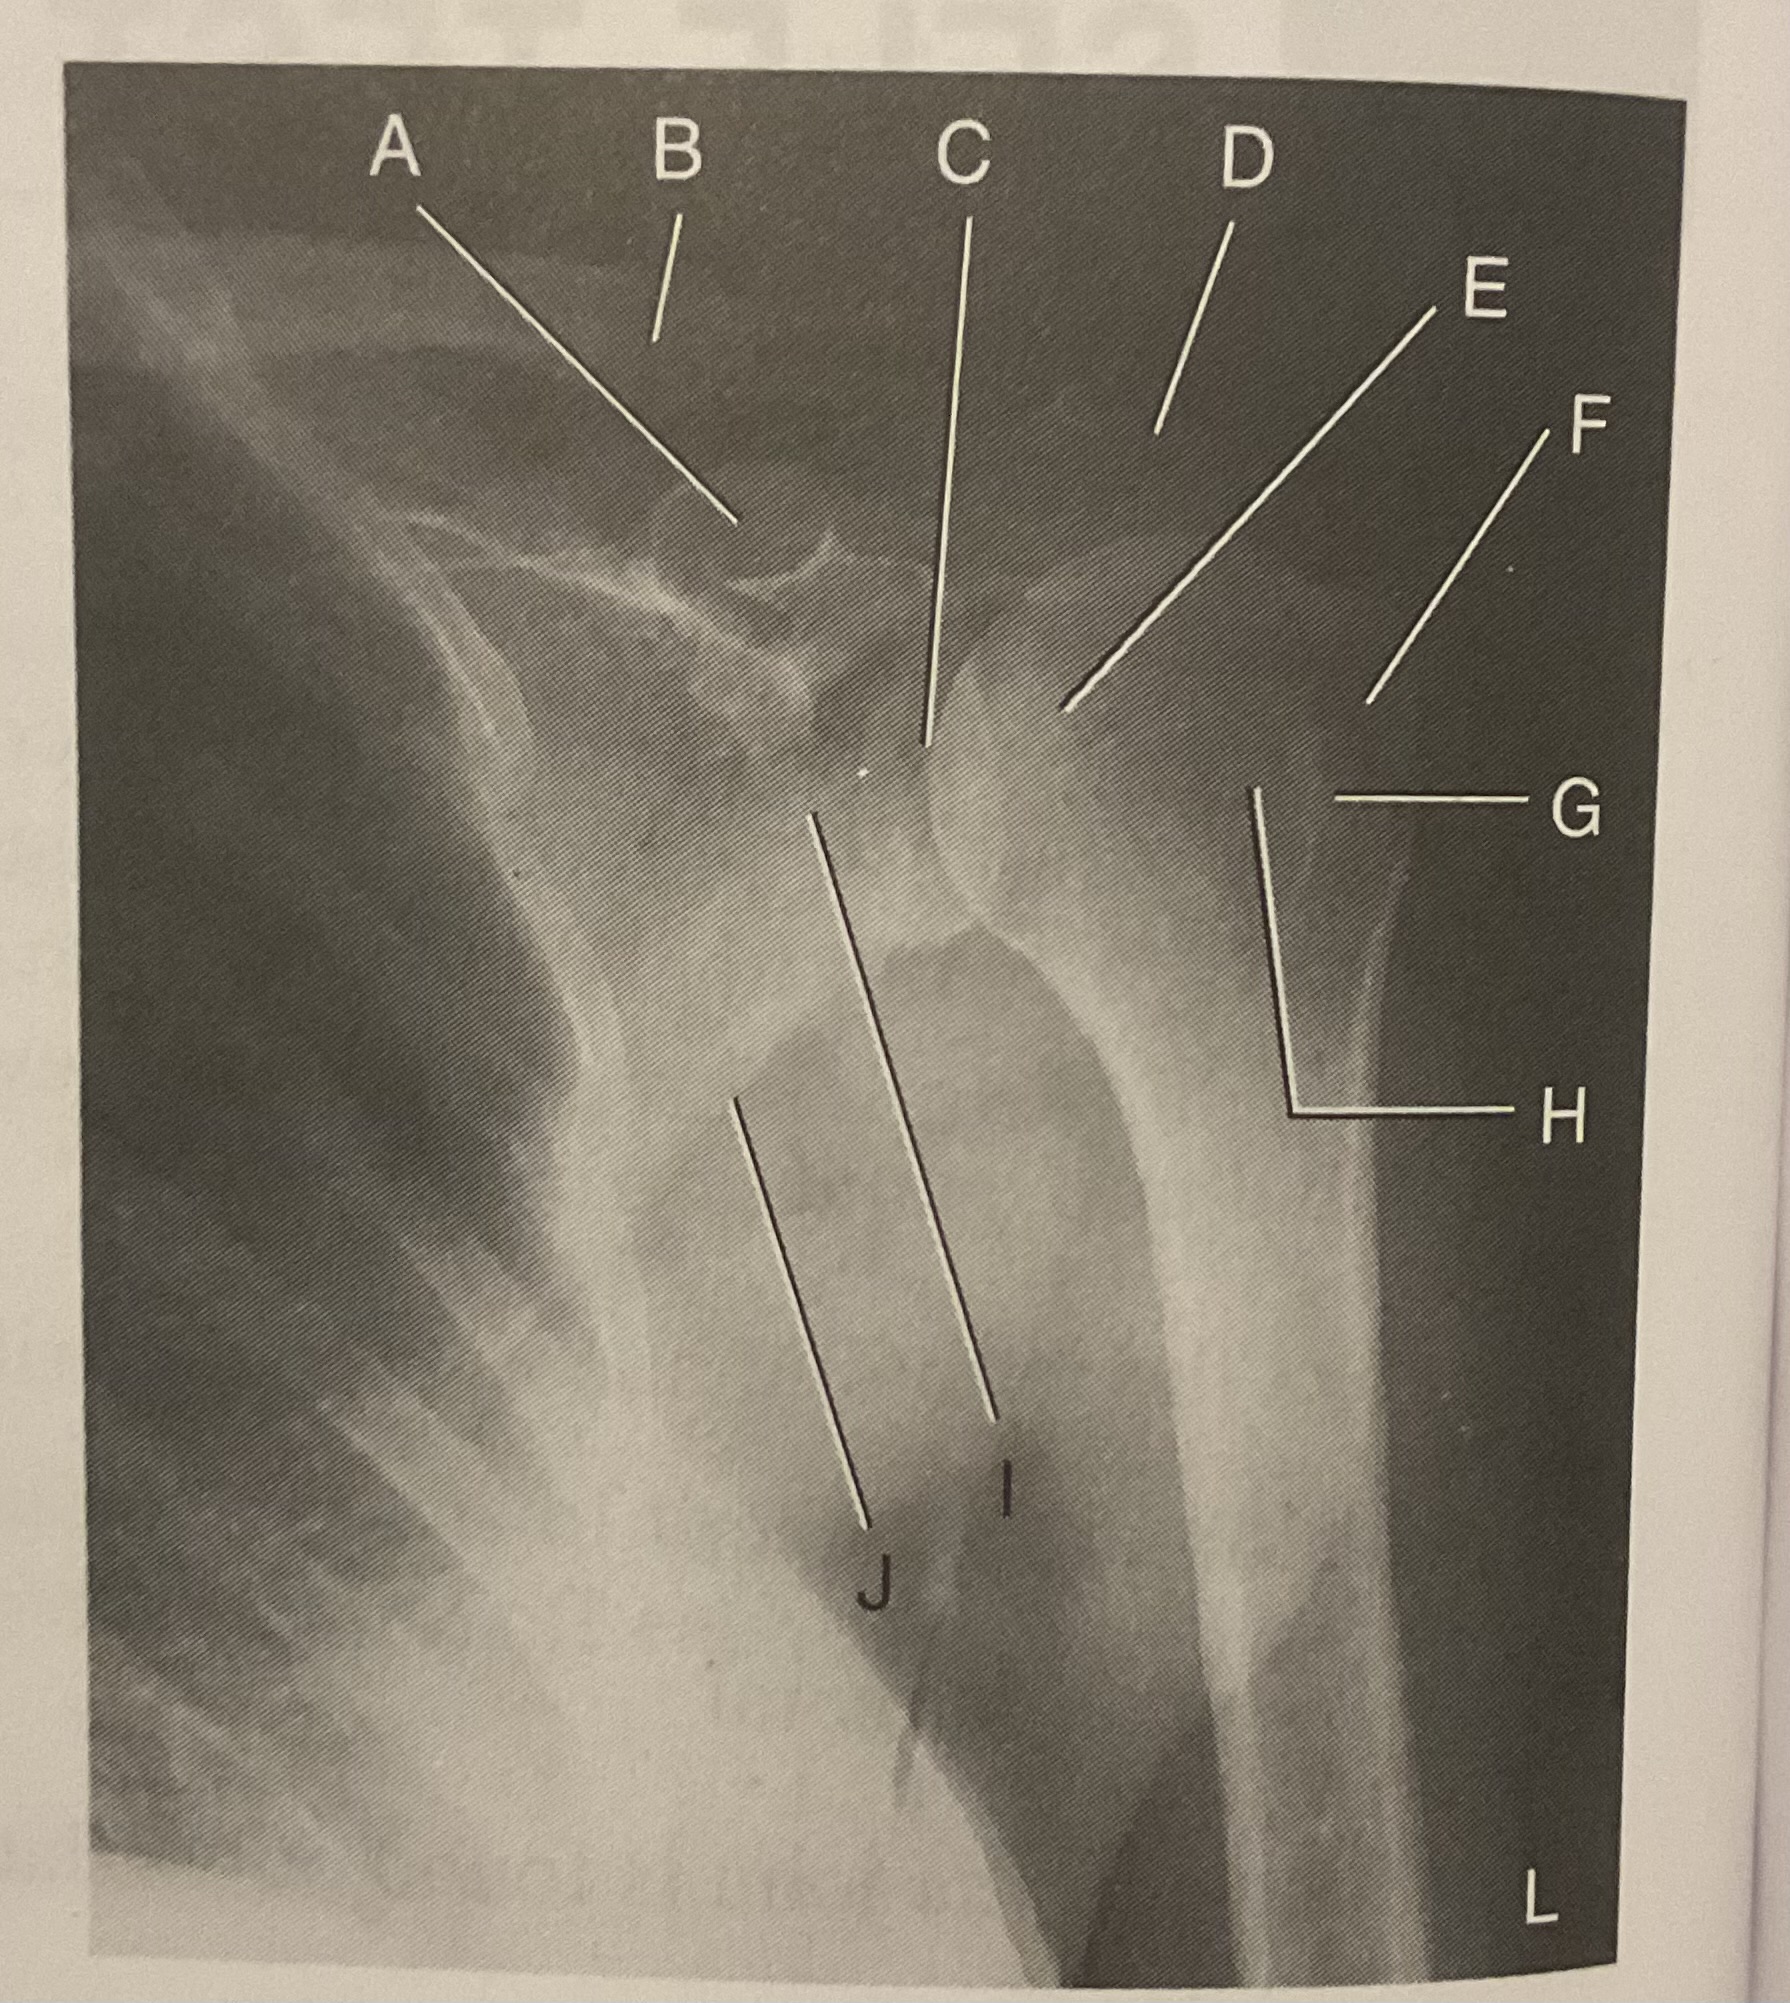

A?

Coracoid process

B?

Clavicle

C?

Scapulohumeral joint

D?

Acromion of scapula

E?

Head of humerus

F?

Greater tubercle

G?

Intertubercular sulcus

H?

Lesser tubercle

I?

Neck of scapula

J?

Lateral (axillary) border of scapula

What AP projection does this image represent?

External